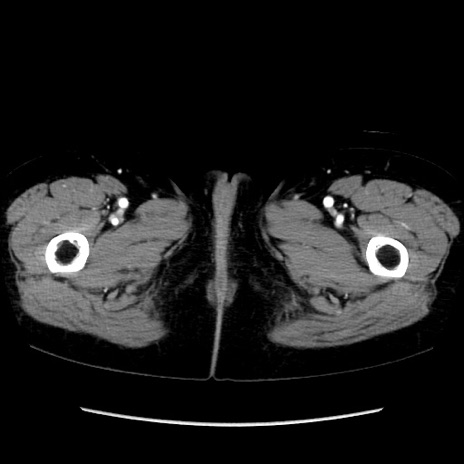

症例32(横断像)

【症例】40歳代 女性

【主訴】上腹部痛、嘔気・嘔吐

【現病歴】約9時間前頃から急に上腹部痛、嘔気、嘔吐が出現。改善しないため救急要請。

【既往歴】子宮頚癌(広汎子宮全摘術、放射線療法)、腸閉塞